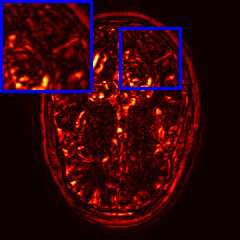

Limited by imaging systems, the reconstruction of Magnetic Resonance Imaging (MRI) images from partial measurement is essential to medical imaging research. Benefiting from the diverse and complementary information of multi-contrast MR images in different imaging modalities, multi-contrast Super-Resolution (SR) reconstruction is promising to yield SR images with higher quality. In the medical scenario, to fully visualize the lesion, radiologists are accustomed to zooming the MR images at arbitrary scales rather than using a fixed scale, as used by most MRI SR methods. In addition, existing multi-contrast MRI SR methods often require a fixed resolution for the reference image, which makes acquiring reference images difficult and imposes limitations on arbitrary scale SR tasks. To address these issues, we proposed an implicit neural representations based dual-arbitrary multi-contrast MRI super-resolution method, called Dual-ArbNet. First, we decouple the resolution of the target and reference images by a feature encoder, enabling the network to input target and reference images at arbitrary scales. Then, an implicit fusion decoder fuses the multi-contrast features and uses an Implicit Decoding Function~(IDF) to obtain the final MRI SR results. Furthermore, we introduce a curriculum learning strategy to train our network, which improves the generalization and performance of our Dual-ArbNet. Extensive experiments in two public MRI datasets demonstrate that our method outperforms state-of-the-art approaches under different scale factors and has great potential in clinical practice.